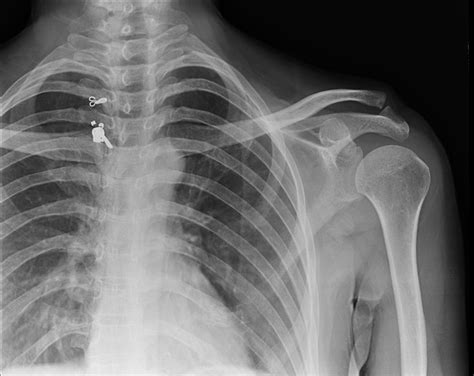

Understanding the intricacies of the X Ray Shoulder Joint is crucial for both medical professionals and patients alike. The shoulder joint is one of the most complex and mobile joints in the human body, making it susceptible to a variety of injuries and conditions. An X-ray of the shoulder joint provides valuable insights into the structure and health of this critical area, aiding in accurate diagnosis and effective treatment.

The shoulder joint is a ball-and-socket joint composed of three main bones: the humerus (upper arm bone), the scapula (shoulder blade), and the clavicle (collarbone). The joint is stabilized by a network of muscles, tendons, and ligaments, which allow for a wide range of motion. Understanding the anatomy is essential for interpreting X Ray Shoulder Joint images accurately.

X-rays are a primary diagnostic tool for various shoulder conditions. Some of the most common conditions that can be identified through an X Ray Shoulder Joint include: